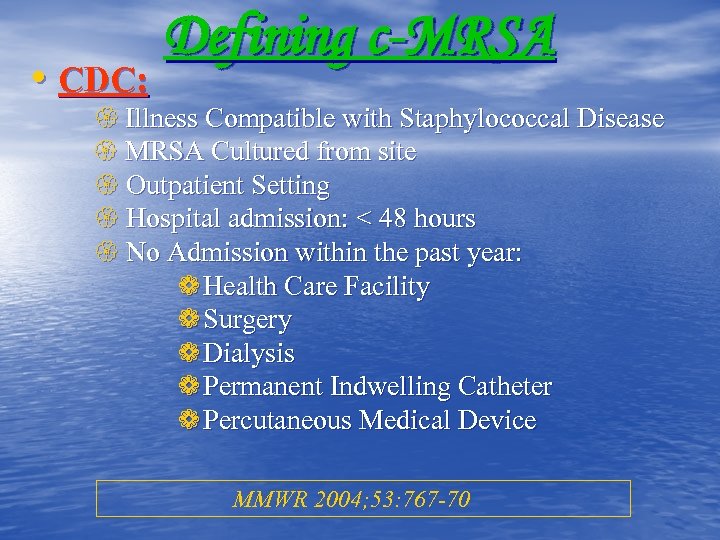

• CDC: Defining c-MRSA Illness Compatible with Staphylococcal Disease MRSA Cultured from site Outpatient Setting Hospital admission: < 48 hours No Admission within the past year: ❁Health Care Facility ❁Surgery ❁Dialysis ❁Permanent Indwelling Catheter ❁Percutaneous Medical Device MMWR 2004; 53: 767 -70

• CDC: Defining c-MRSA Illness Compatible with Staphylococcal Disease MRSA Cultured from site Outpatient Setting Hospital admission: < 48 hours No Admission within the past year: ❁Health Care Facility ❁Surgery ❁Dialysis ❁Permanent Indwelling Catheter ❁Percutaneous Medical Device MMWR 2004; 53: 767 -70